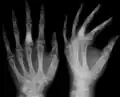

X-ray showing calcified enchondromas localized in finger a 37-year-old patient affected with Ollier disease -